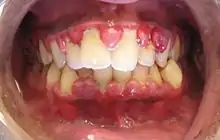

![]() | |

| Gingival enlargement can be a feature in some periodontal diseases. | |